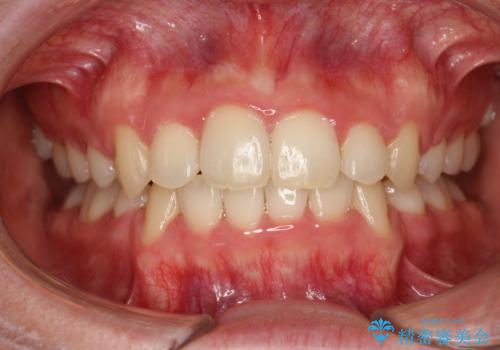

ワイヤーによる抜歯矯正でガタガタと深いかみ合わせの改善